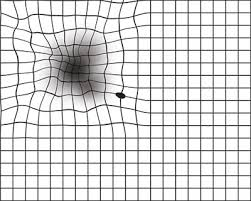

手机看多了眼睛干涩?简单的阿姆斯勒方格测试,自测黄斑病变风险

眼睛是人类感知外界 80% 信息的来源。 定期进行简单的自测,科学使用电子设备,别让窗外的美景变成模糊的背影。

黄斑变性的临床表现与症状

你有没有过这样的经历:看书时发现字体变得模糊,看人脸时感觉五官扭曲,或者盯着某个地方时总觉得中间有个黑影?如果有,那你可能需要关注一下黄斑变性这个"视力杀手"了...